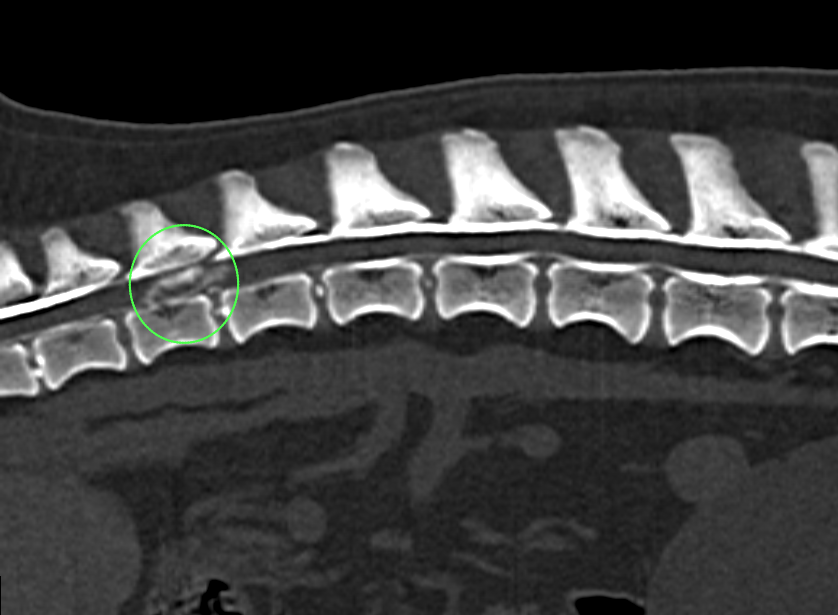

• 椎間板ヘルニア

骨盤骨折 椎間板ヘルニア